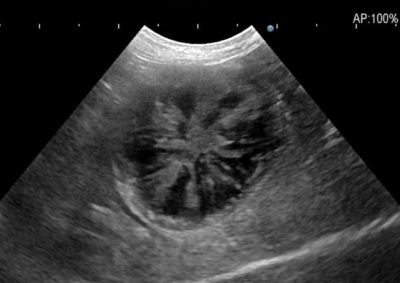

軟部組織外科 注意 ボタンをクリックした先に、治療中および手術中の画像が説明で使用されている場合がございます。 そのような画像に弱い方は閲覧なさらないようお願いいたします。 軟部組織外科腫瘍外科 ジャックラッセルテリアの胃腫瘍 救急・集中治療軟部組織外科 呼吸困難を起こした唾液瘤 軟部組織外科救急・集中治療呼… 喉頭麻痺 軟部組織外科 胆嚢粘液嚢腫 軟部組織外科救急・集中治療 胃捻転拡張症候群 GDV 軟部組織外科腫瘍外科 大腸腺癌 軟部組織外科腫瘍外科 肺葉切除術 軟部組織外科腫瘍外科 唾液腺癌 Salivary gland carcinoma 軟部組織外科救急・集中治療 鼠径ヘルニア嵌頓による腸閉塞 軟部組織外科腫瘍外科 胃部分切除術・ビルロートI 軟部組織外科 門脈シャント 軟部組織外科内科 猫の会陰尿道瘻設置術 <«89101112131415> 症例カテゴリー 放射線治療整形外科軟部組織外科脳神経外科内科腫瘍外科救急・集中治療リハビリテーション科腫瘍内科内視鏡科脳神経科呼吸器外科中医・漢方猫の腎移植循環器科